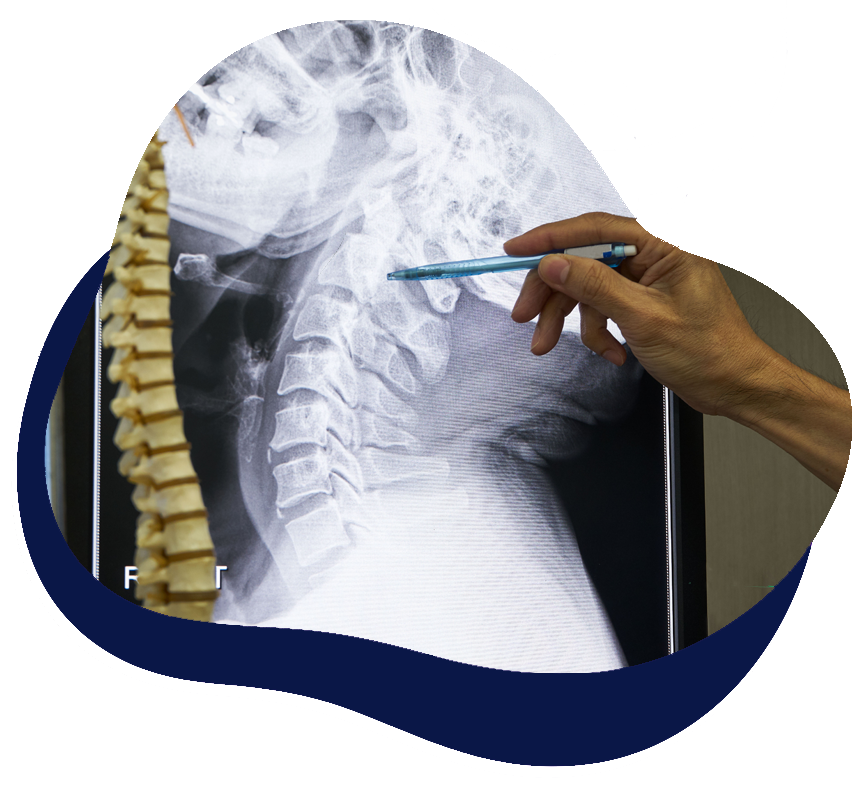

Complex Spine Surgery

Complex spine Surgery include procedures which are more difficult than simple discectomy, laminectomy or 1 or 2-level spinal fusion. The conditions for which complex spine surgery may be a solution include degenerative scoliosis (curvature of the spine which comes on during the aging process), cases of malignant spine tumors, cases of severe spinal trauma, or cases in which there is significant misalignment of the spinal vertebrae, such as in Spondylolisthesis. Spondylolisthesis is found when one of the spine vertebra slips forward significantly on the one below it.

Anterior and posterior, cervical, thoracic, and lumbosacral instrumented spinal fusion operations are examples of complex spine surgery that our physicians perform on a regular basis.

Complex Spine — MRI Pathology Examples

Each region displays a representative pathology commonly treated in complex spine surgery.